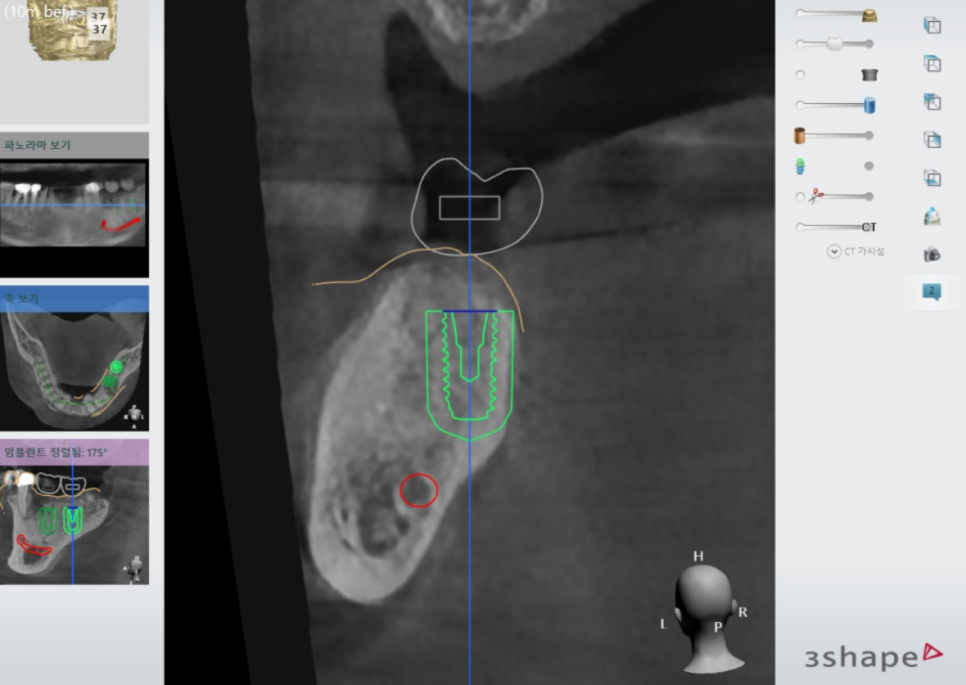

예측도 가능하여

모의 수술을 진행해보기 때문에

무절개 임플란트 수술이 가능한건데요.

| 1) ct로 분석 |

|---|

| 2) 네비게이션 기술 활용 |

| 3) 발치와 동시에 수술 |